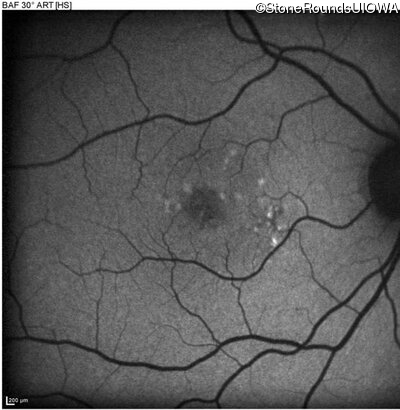

Blue Autofluorescence - Right - 20/20 +1

Exemplar

Blue Autofluorescence - Left - 20/63 -1

Blue Autofluorescence - Right - 20/20 -2

Blue Autofluorescence - Left - 20/50

Blue Autofluorescence - Right - 20/20

Blue Autofluorescence - Left - 20/63